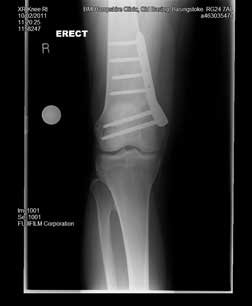

These are the two X-rays showing the femur with the plate in position from the front (left image) and the side (right image).